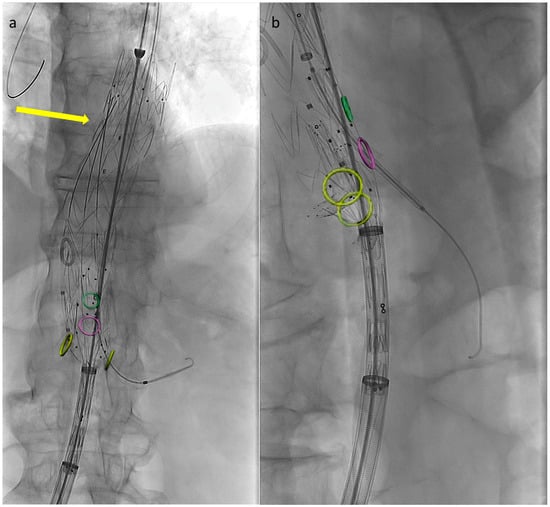

In order to perform partial endograft deployment, the device should be prepared before insertion by advancing, under fluoroscopy, all four dedicated 400 cm long 0.018″ non-hydrophilic guidewires through the corresponding microcatheters until their proximal end reaches the cranial graft’s edge (Figure 1).

Figure 1. Fluoroscopic check during guidewire anticipated advancement. Graft leaning on patient body (a), yellow arrow pointing at the tip of the first positioned guidewire (b), second guidewire advancement (c) and final results after all guidewires have been correctly advanced (d).